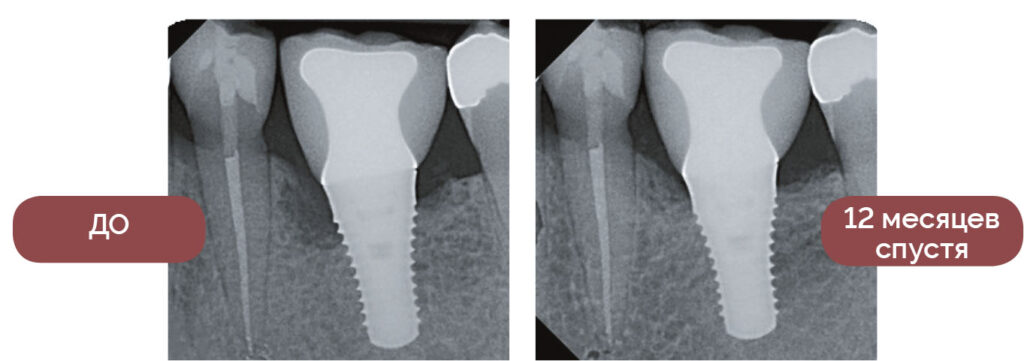

ЛЕЧЕНИЕ ПЕРИИМПЛАНТИТА

— Waterlase — неотъемлемая часть моей практики. Почти каждый день я стараюсь спасти имплантат с признаками отторжения, вылечить зуб с пародонтальной патологией, взять биопсию образования или устранить дефекты мягких тканей. Я не могу представить свою работу без Waterlase и настоятельно рекомендую каждому стоматологу пользоваться этим инструментом. Ваши пациенты будут благодарны.